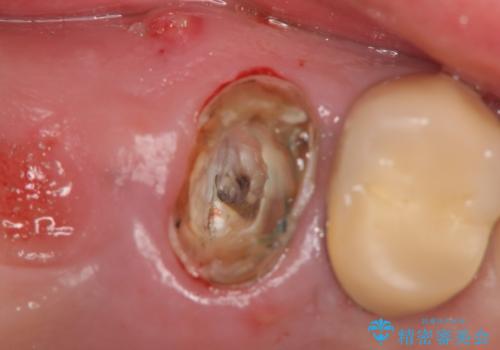

- 右上のブリッジでものを咬むと違和感があり、歯茎に膿の出口もできているので診て欲しいといらっしゃった方の症例です。

右上の567ブリッジを外したところ、右上5は歯根破折により保存不可能だったため、右上56部にインプラントを埋入し欠損補綴を行いました。

また右上5部に関しては抜歯時に歯槽堤保存術(抜歯窩に人工骨の填入を行う手術)を行い、骨の欠損を最小限に止めています。